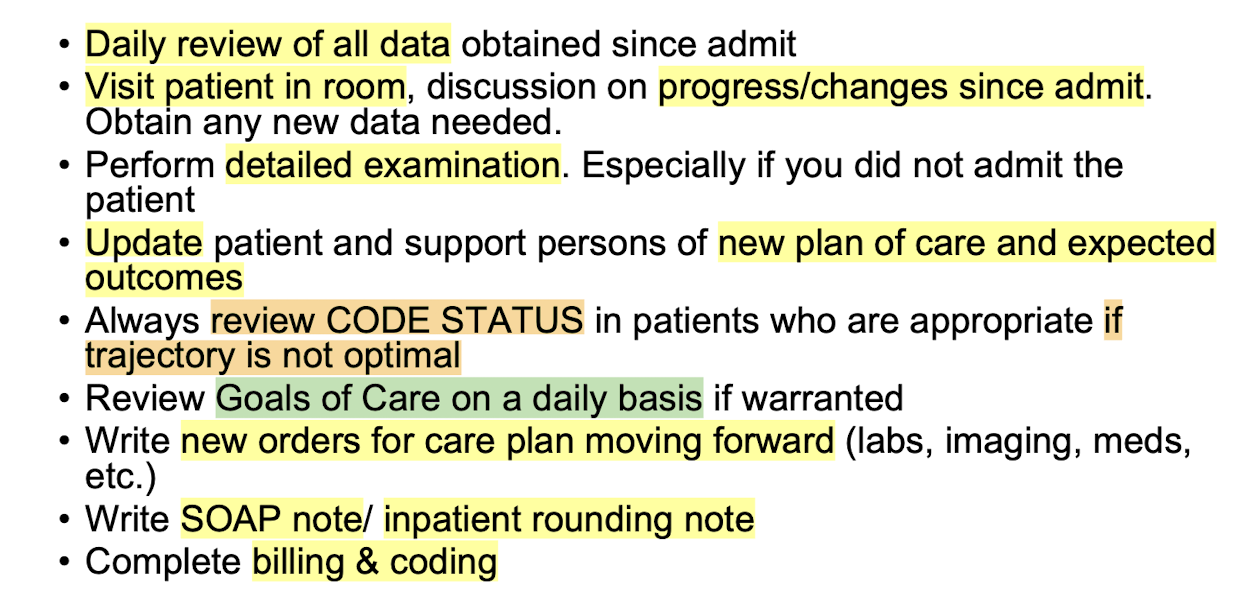

Daily Rounding

-Every day the new data creates an evolving care plan with the interprofessional team

-Attending provider makes the ultimate decisions on plan of care

-New data is collected, new orders are placed, and new documentation is created

Steps: